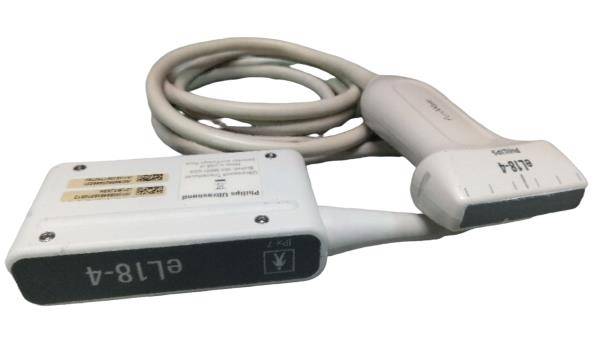

2017 GE IC9 -RS probe for GE Ultrasound

Sale price$ 8,395.14